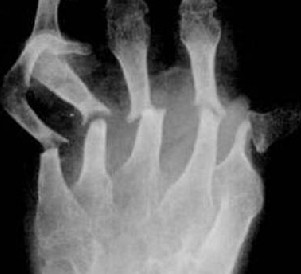

• 得了类风湿性关节炎需要做哪些检查呢

类风湿性关节炎常伴有晨僵。类风湿性关节炎关节强直和掌指关节半 ...